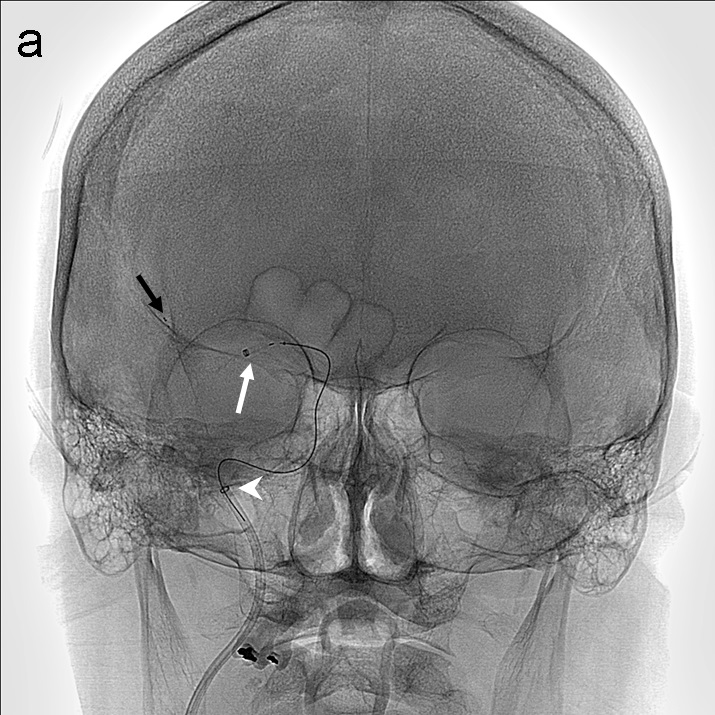

Tras la punción femoral derecha se asciende catéter balón FlowGate2 asistido por el catéter guía de asistencia punta Berenstein con guía de Terumo 0.035’’ para la cateterización de la arteria carótida común derecha y realización de estudio diagnóstico. Se obtienen series angiográficas en proyecciones anteroposterior y lateral de craneo que demuestran la presencia de trombo en el segmento M1 proximal de la ACM derecha (imagen 1). A continuación, mediante roadmap, cateterizamos la ACI derecha y realizamos un primer pase de trombectomía usando la técnica ADAPT a través del FlowGate2 con el AXS Catalyst 5 como catéter de aspiración, Trevo Pro 18 como microcatéter y con la microguía Asahi Chikai 0.014’’.

La técnica ADAPT consiste en usar el microcatéter y la microguía con el fin de facilitar la navegación del catéter de aspiración hasta aproximadamente 1-2 cm del trombo, momento en el que se retiran la microguía y el microcatéter y la llave en ‘Y’ avanzando el catéter de aspiración hasta que deja de refluír sangre por el ‘hub’. Tras esto se conecta la bomba de aspiración, se hincha el balón del FlowGate2 (imagen 2) con contraste diluido (50:50), se aspira con una jeringa de 50 cc través de éste último y se realiza el pase retirando el catéter aspiración.